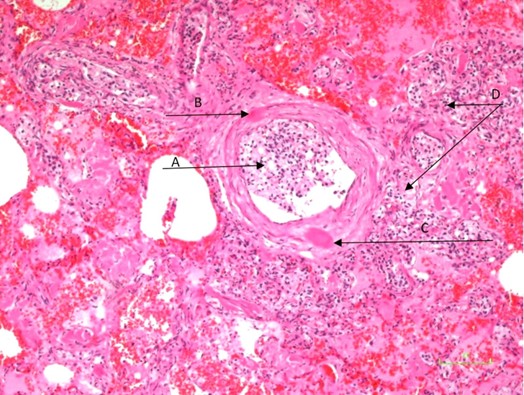

Xanthogranulomatous Pyelonephritis: An Uncommon Form of Pyelonephritis Highlighted in a Case Report

Danielle Malavazi Oliveira; Bárbara Sthefany de Paula Lacerda; Matheus Compart Hemerly, Maria Isabel Lima dos Santos, Weverton Machado Luchi